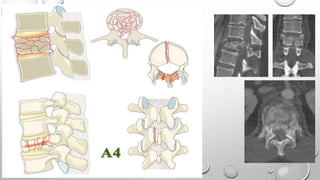

Tipo A

Describen daño del cuerpo vertebral sin

compromiso de la banda de tensión.

A0: Fractura no estructural, menor

A1: Compresión en cuña

A2: Separación, División

A3: Estallido incompleto

A4: Estallido Completo